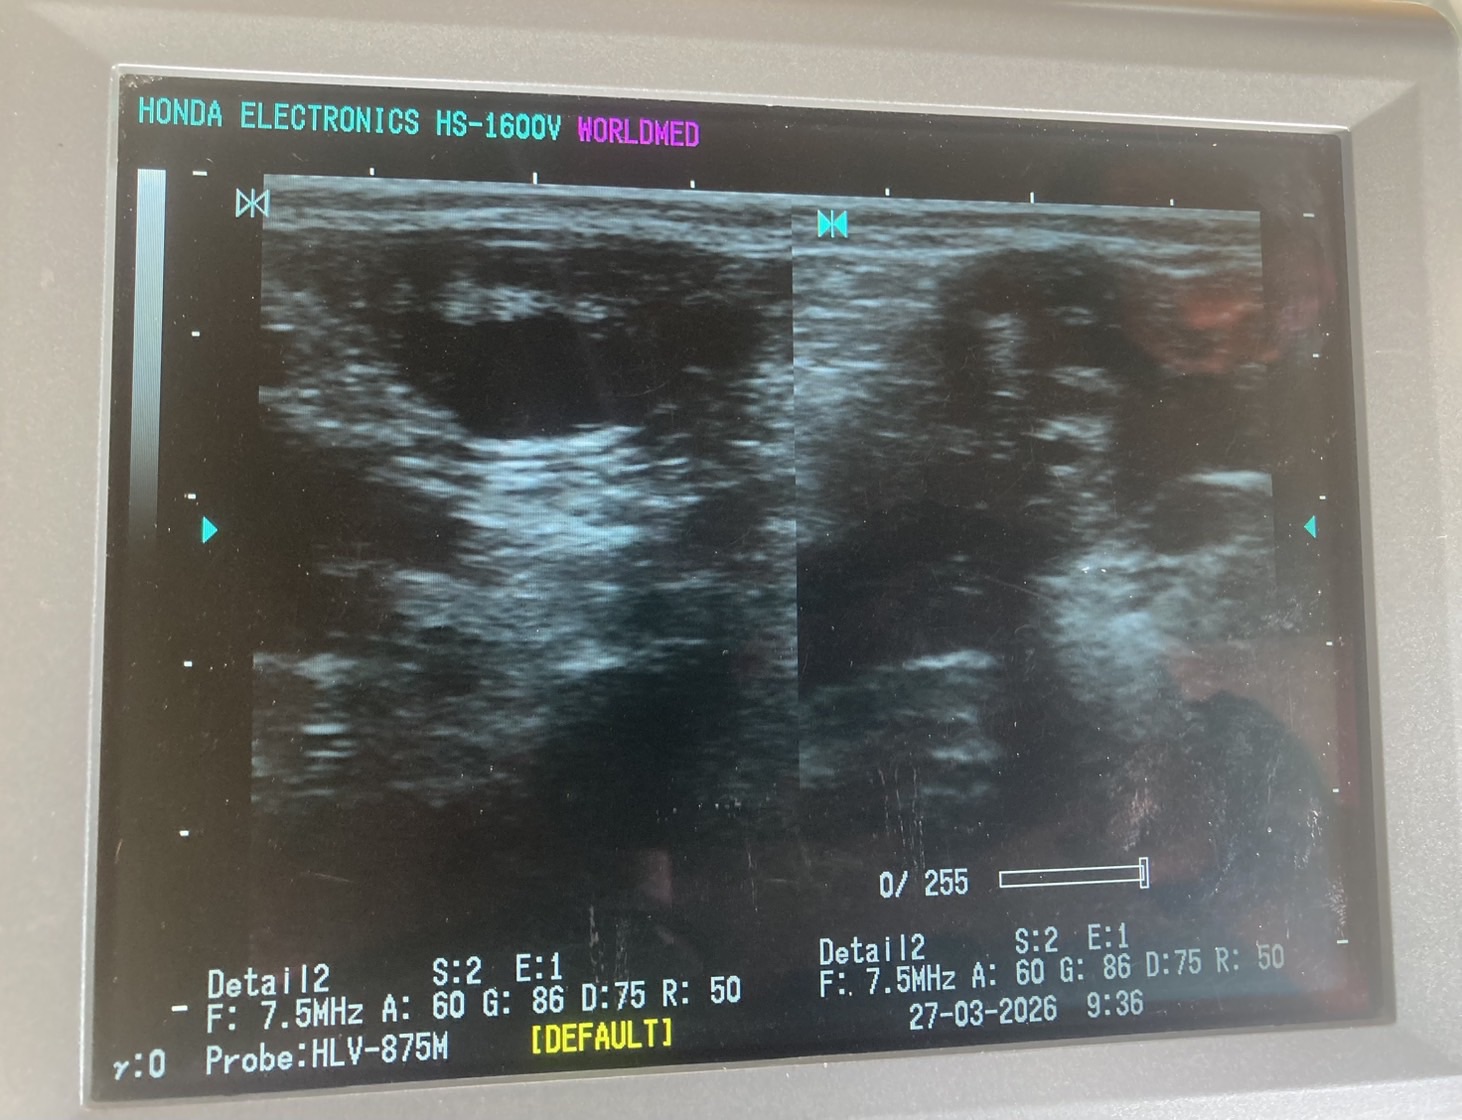

ตรวจท้อง จำนวน 3 ตัว ท้องจำนวน 3 ตัว